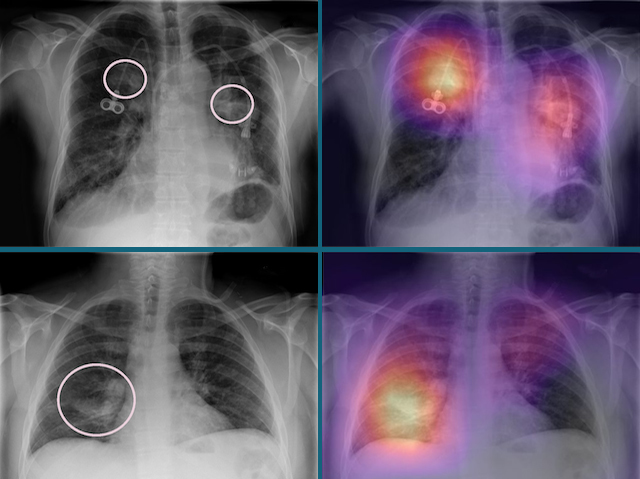

Every year, millions of people worldwide are affected by some kind of lung disease, usually diagnosed with chest X-rays. Unfortunately, there aren’t enough expert radiologists to keep up with analysing all these images, particularly in areas of the world where doctors are in short supply and lack specialist training. As a solution, researchers have developed an artificial intelligence (AI) tool called CheXNeXt to analyse chest X-rays and spot the signs of 14 different lung diseases. For example, the images on the right show brightly coloured ‘heat maps’ that indicate the presence of abnormalities where vein catheters have been inserted (top) while the lower panels are from a patient with pneumonia, which shows up as a white mass on the X-ray. When put to the test, CheXNeXt performs at least as well as expert radiologists, so it could be a useful tool for helping to diagnose lung disease in the future.